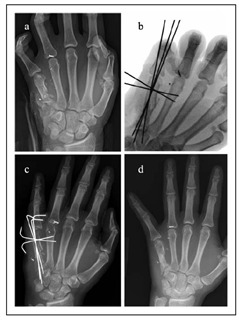

文献1】より(a) 銃撃による第5中手骨骨幹部の粉砕骨折の術前X線写真。 (b) 非観血的整復および経皮的ピンニング後の術中透視像、および(c, d) 術後3週および23週のX線写真。骨折の癒合が進行し、骨のアライメントも良好である。

経皮的ピンニング

骨折の整復後に経皮的ピンニングを行う方法は、依然として一般的な手術固定法です。キルシュナーワイヤー(Kワイヤー)固定は、低侵襲性の選択肢であり、外科医が安定化パターンを柔軟に選択でき、軟部組織への損傷を最小限に抑えることができます。しかし、Kワイヤーは、スクリュー、プレート、釘を用いたより安定した固定法と比較して、固定が失われるリスクが高くなります。

文献1】より